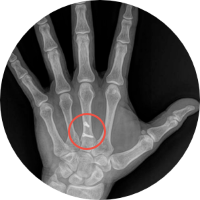

Humanos

• Niños

• Adultos

• Pacientes geriatras

• Seguimiento post cirugía ortopédica

HumanosRadiología Digital Directa

Posteriormente la radiología computarizada evolucionó a la radiología digital directa en donde podíamos hacer placas radiográficas y ver las imágenes en aproximadamente 18-20 segundos después de tomar la radiografía, y esto fue un gran avance para la comunidad de médicos, veterinarios, antropólogos, restauradores, paleontólogos, investigadores, y gente que requería radiografías y que por la logística que se requería y lo que implicaba no utilizaba esta herramienta de diagnóstico. En la actualidad, en la era de la inmediateidad podemos tomar placas radiográficas de alta definición en 2-3 segundos, en lugares remotos, sin necesidad de energia electrica ya que los generadores de rayos X funcionan con baterías, así como los equipos de radiología digital directa, esto ha permitido que el servicio de radiología se pueda proporcionar en cualquier lugar donde se requiera, pudiendo llevarse a donde están los pacientes u objetos a radiografiar, con las ventajas que esto implica. Los equipos actuales son ligeros, portátiles, de alta frecuencia, de alta definición, se ha optimizado la radiación que generan, lo que permite obtener imágenes radiográficas de muy buena calidad, con técnicas radiográficas inferiores a lo que se requería con radiología análoga. Hoy en día manejamos radiología digital directa de alta resolución.

Ideal para pacientes con incapacidad para trasladarse al hospital o moverse. Fracturados, con fijación externa, osteoporosis, niños, adultos, pacientes geriatras, seguimiento post cirugía ortopédica.